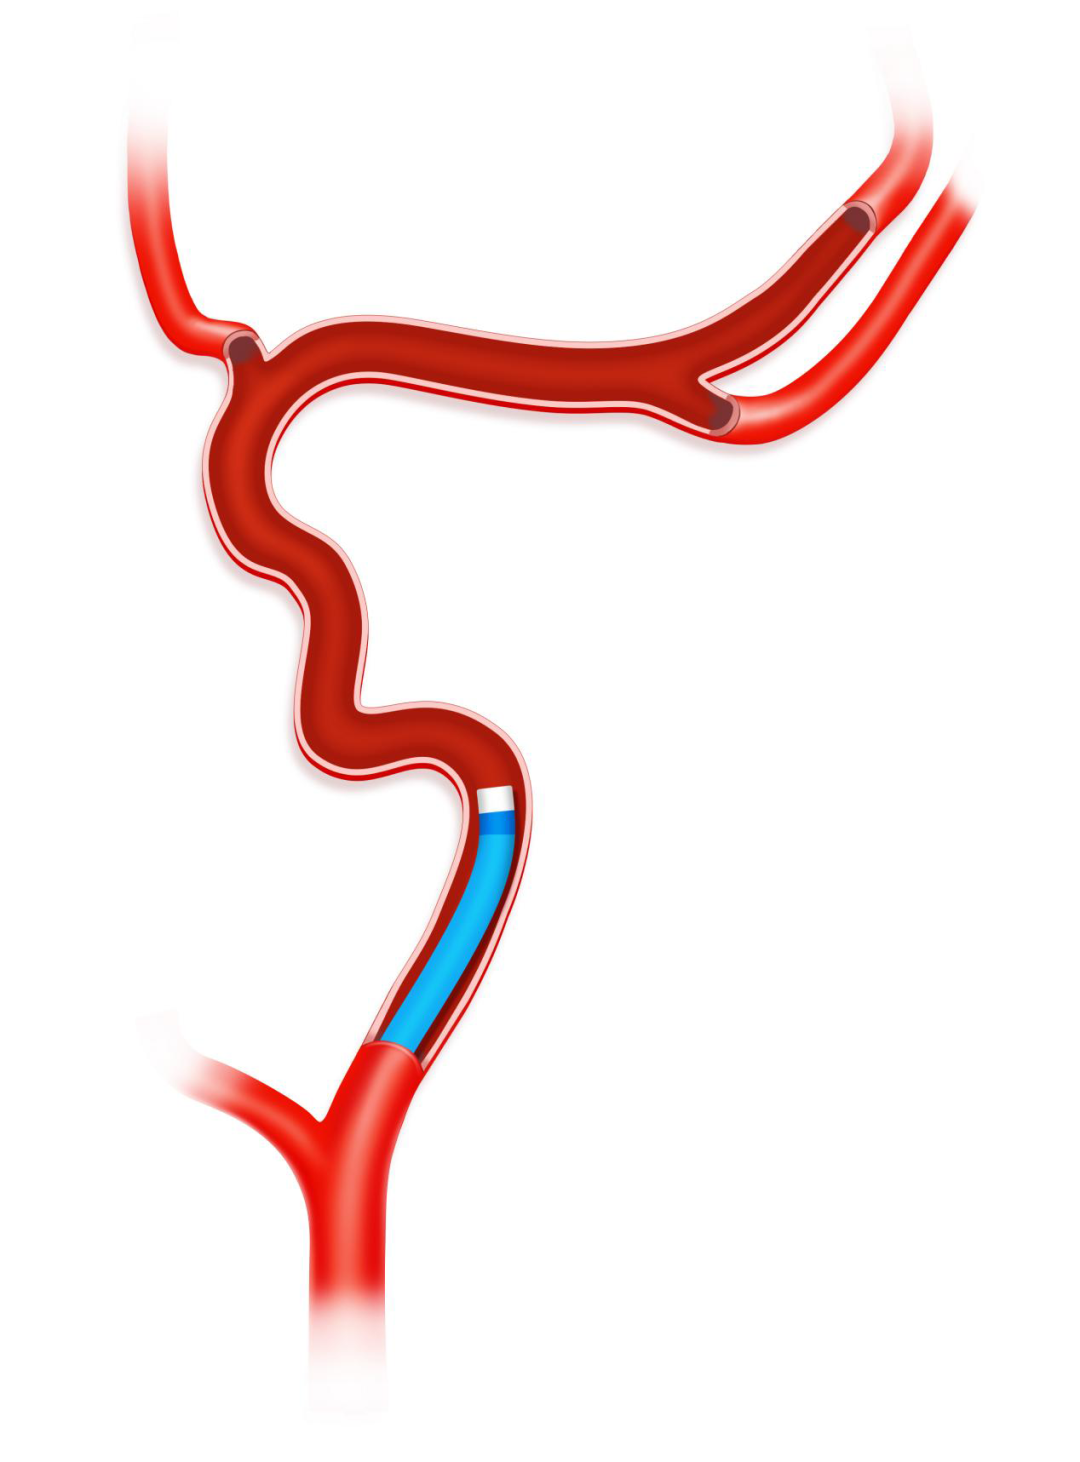

AOSIS技术(Acute large vessel OccluSion recanalization with the Intracranial protection of Stent retriever,颅内取栓支架保护下的急性大血管闭塞开通术)是基于加奇生物 Syphonet®取栓支架的独特设计特点而衍生出的针对急性大血管闭塞开通实施颅内保护的技术,在颅内动脉急性闭塞,血栓抽吸导管新手很难到位接触抽吸血栓,取栓过程容易栓子逃逸问题,利用3.0*25mm Syphonet®取栓支架作为颅内保护装置在闭塞血管远端锚定,支架远端有网篮设计,可以捕获逃逸血栓而起到保护伞的作用,近端跟进Tethys AS®血栓抽吸导管至血栓近端,关闭滴注打开血栓抽吸导管Y阀状态下越过血栓,回收支架至血栓抽吸导管内,最后将Syphonet®及Tethys AS®整体撤出。同时,Syphonet®取栓支架适配0.017、0.021inch的微导管,较小的微导管超选后,可直接将支架输送至远端释放,锚定支撑能力较强。

沿17或21系列微导管输送并释放3.0*25mm Syphonet®取栓支架,支架近段覆盖大脑中动脉闭塞病变部位,支架远端到达大脑中动脉M2。利用Syphonet®取栓支架的锚定作用和远端防血栓逃逸保护作用。

Syphonet®取栓支架锚定作用下跟进Tethys AS®血栓抽吸导管,靠近血管病变处开始关掉滴注,打开血栓抽吸导管Y阀后,越过大脑中动脉闭塞处到达大脑中动脉M1段末端。

负压下将Syphonet®取栓支架和Tethys AS®血栓抽吸导管一起撤出,造影确认再通后结束手术。

手术示意图

本例全程在局麻下完成,术中我们采取AOSIS技术来进行本例开通血管,远端取栓支架锚定,利用Syphonet®取栓支架抓捕篮作为保护,近端Tethys AS®血栓抽吸导管关闭滴注越过血栓进行抽吸取栓,这样使血栓抽吸导管迅速到位充分接触血栓,并且远端有取栓支架保护,减少血栓逃逸的风险,极大提高血管再通效率,实现安全开通。